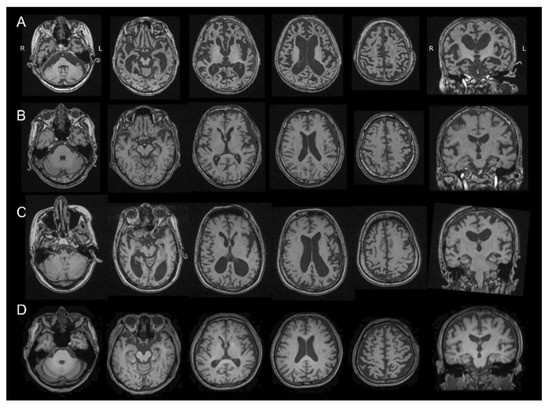

2.2. MRI Study